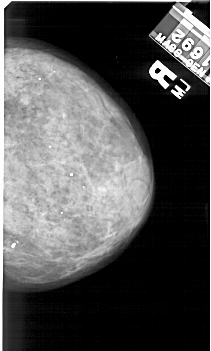

A_1420_1.LEFT_CC

LEFT_CC LINES 5176 PIXELS_PER_LINE 2791 BITS_PER_PIXEL 12 RESOLUTION 43.5 OVERLAY

FILE: A_1420_1.LEFT_CC.OVERLAY

TOTAL_ABNORMALITIES 1

ABNORMALITY 1

LESION_TYPE CALCIFICATION TYPE AMORPHOUS DISTRIBUTION CLUSTERED

ASSESSMENT 4

SUBTLETY 2

PATHOLOGY BENIGN

TOTAL_OUTLINES 1

BOUNDARY